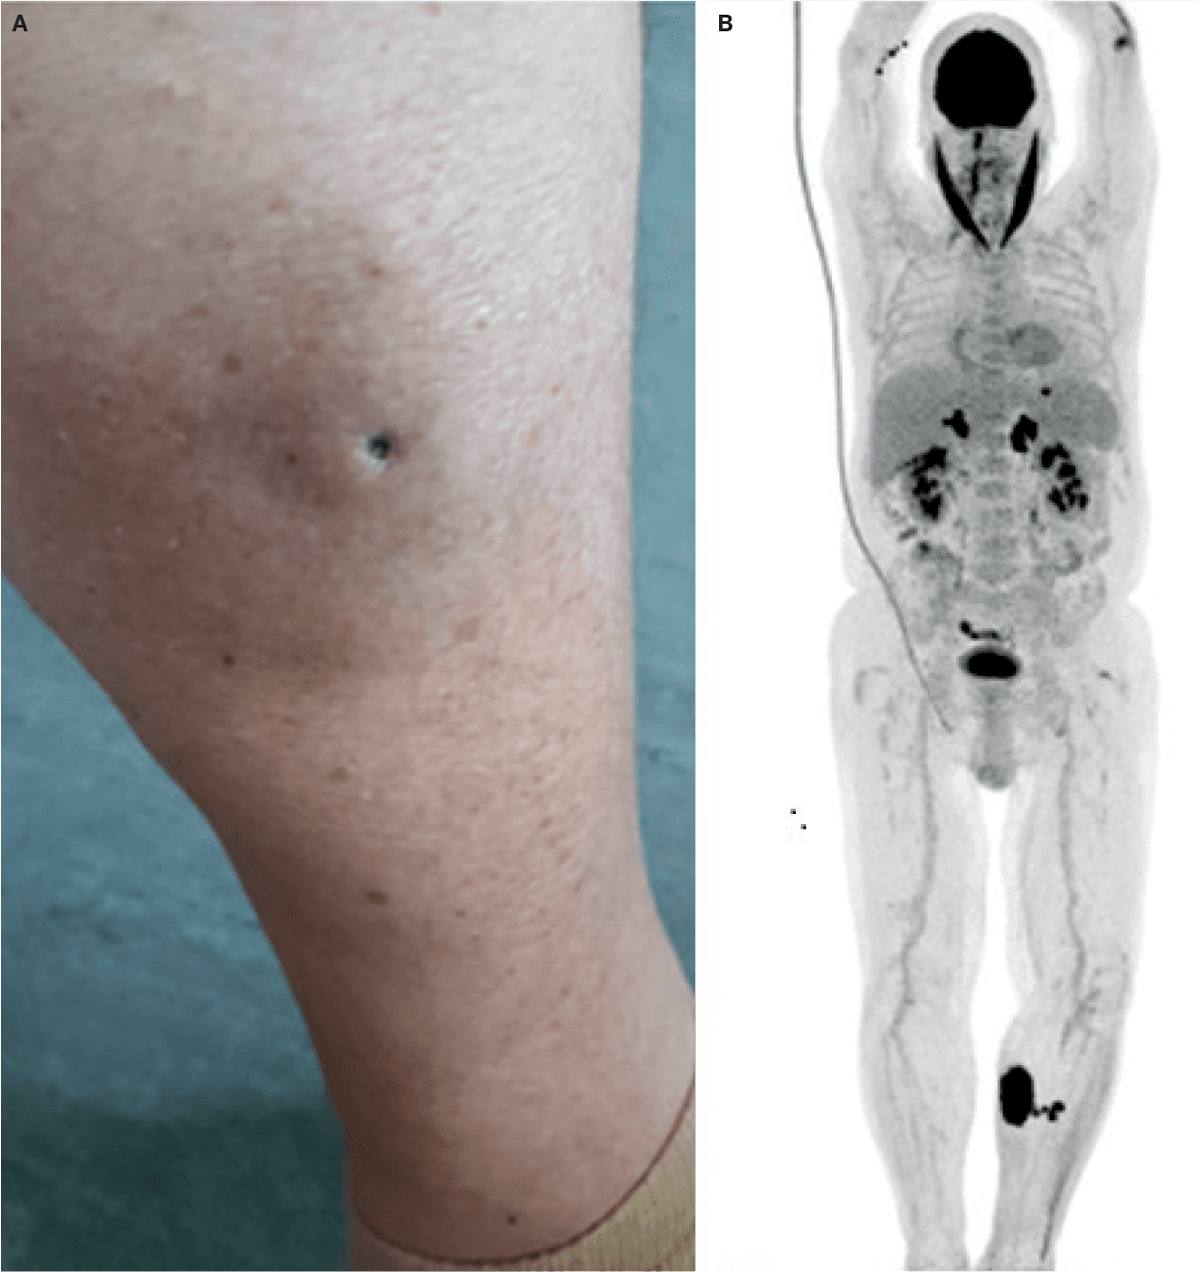

Klinisk sås et infiltreret, indureret og let erytematøst 10 × 10 cm-element på mediale crus og et tilsvarende mindre på laterale crus. Diagnostisk blev der overvejet panniculitis, og der blev taget en dyb 4-mm-stansebiopsi fra mediale crus, hvilket medførte en central sårdannelse (A). Histologien viste et højmalignt DLBCL med samme markørprofil som det tidligere CNS-lymfom. Før histologisvaret var modtaget, blev patienten indlagt akut i andet regi med tiltagende gangbesvær. Helkrops-18F-fluordeoxyglukose (FDG)-PET-CT viste høj FDG-optagelse i venstre crus (B), binyrer og colon transversum. MR-skanning af columna totalis viste myelitis som muligt paraneoplastisk fænomen. Diagnosen var ekstracerebralt recidiv af CNS-lymfom.